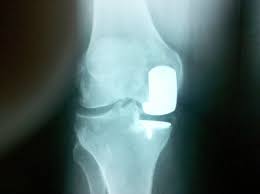

3. Implant Placement: A metal and plastic prosthesis is positioned to replace the damaged surfaces, preserving the healthy tissue in the unaffected compartments.